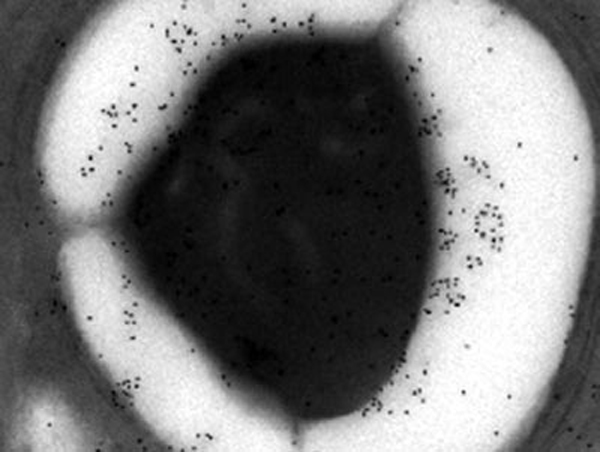

El almidón modificado podría curar el paludismo

El almidón, una cadena de azúcares, es la principal reserva de energía en el maíz y la papa.